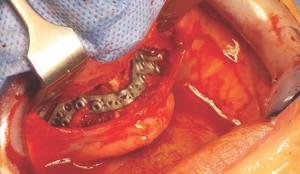

Following careful informed consent, the patient was treated in the OMFS Department in Ninewells Hospital. The first surgical stage was completed with a bimaxillary osteotomy with 3D guides and plates (KLS Martin) followed by bone grafts from the left iliac crest to the maxilla and mandible (Figure 5). The maxilla was advanced 10mm and set down 7mm.

The piezoelectric system was very important in the management of this patient. It was used to split the maxillary and mandibular ridges (UR4, UR1, LL3 and LR2 regions) and also to remove the bone and open the alveolar ridge anteriorly and posteriorly on the right side of the maxilla.

Bone level fixtures were placed in the intraforaminal region with submerged healing, and axially loaded. After alveolar ridge height reduction to facilitate implant placement in the apico-coronal position, one Southern zygomatic implant (Zygex with uniabutment and healing cap) was placed in the left quadrant and three 10mm bone-level implants (021.3310) were placed (UR4, UR1 and UL1 sites) (Figure 6). Two 12mm implants (021.5310)) were then placed in the mandible (LL3, LR2 regions).